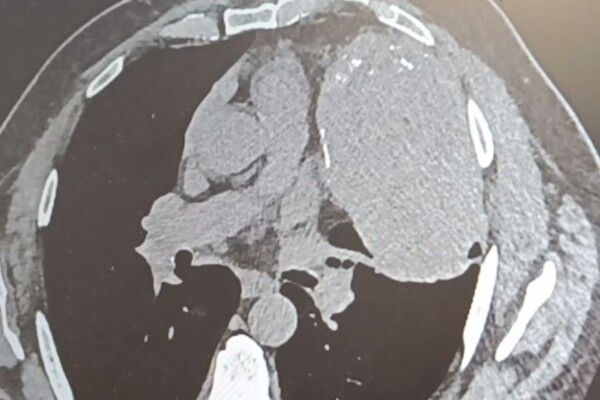

Снимок внутренних органов. Источник: Минздрав Оренбургской области В Оренбурге врачи удалили огромное новообразование в грудной клетке у жителя Орска, которое начало формироваться между сердцем,

Снимок внутренних органов. Источник: Минздрав Оренбургской области В Оренбурге врачи удалили огромное новообразование в грудной клетке у жителя Орска, которое начало формироваться между сердцем, правым легким и ребрами около 20 лет назад.

Ранее новообразование не мешало пациенту, поделились в Минздраве. Со временем оно сильно увеличилось, заполнило пространство в грудной клетке и стало сдавливать легкое. Усугубилась ситуация в 2024 году, когда мужчина заболел пневмонией. Его направили в ООКБ №2, чтобы сделать операцию.

Продлилась операция почти 3 часа. Работу осложняло близость новообразования к крупнейшим кровеносным сосудам и сердцу. Однако хирурги со своей задачей справились успешно.